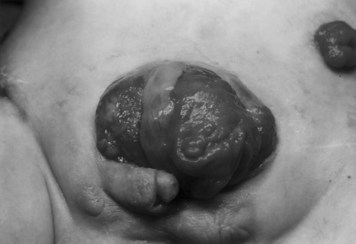

Because of the significant separation of the corpora of the penis and scrotum and the reduction in corporal size noted in boys with cloacal exstrophy, early reports had recommended universal gender reassignment of boys (46,XY) with cloacal exstrophy to functional females (Tank and Lindenaur, 1970). To this end, bilateral orchiectomy was combined with phallic reconstruction as a functional clitoris and early or delayed vaginoplasty. Reiner (2004) has reported on 29 males with cloacal exstrophy who had gender reassignment to female. Psychosexual evaluation indicated that all of these patients had a marked male shift in psychosexual development despite having no pubertal hormonal surges. A comparison of patients with cloacal exstrophy and other cloacal anomalies at the Great Ormond Street, however, indicated no difference in social or behavioral competence or psychologic problems. Gender assignment was not associated with childhood psychologic, emotional, or behavioral problems (Baker Towell and Towell, 2003). Schober and colleagues (2002), reporting on 14 children who had undergone early gender reassignment, indicated that although patients had masculine childhood behavior, they had a feminine gender identity. Currently, however, most authors recommend assigning gender that is consistent with karyotypic makeup of the individual if at all possible (Fig. 124–30). This policy can be supported by a report indicating that the histology of the testis at birth is normal (Mathews et al, 1999a). Furthermore, with evolution of techniques for phallic reconstruction, a functional and cosmetically acceptable phallus can now be constructed (Husmann et al, 1989).

Reconstruction of the external genitalia in the immediate postnatal period is performed to make the infant appear more congruent with the gender assigned. The psychiatric studies of children who have had gender assignment have fueled interest in male gender assignment if adequate unilateral or bilateral corporal tissue is present (Reiner, 2004). Histologic studies indicate normal histology in the testes of male subjects who have had gender reassignment despite the presence of cryptorchidism (Mathews et al, 1999a). Results of phallic reconstruction in male patients with minimal or no penile tissue in the past have been disappointing. For male-to-female reassignment, initial female genital reconstruction should bring the phallic halves together in the midline as a clitoris.